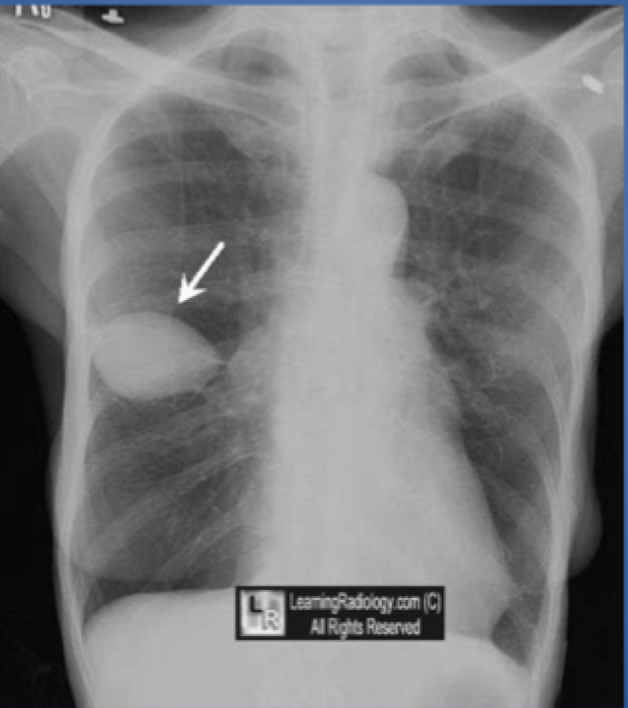

Loculated effusion CXR

A

-effusion may appear loculated (~mass/pseudotumor) if there are pleural adhesions